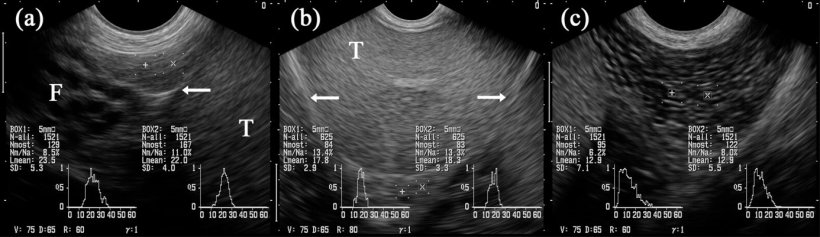

En general, el tejido del epidídimo es también de ecotextura homogénea y regular, siendo más fina en la cabeza y el cuerpo y un poco marmoleada en la cola (figura 5A-C). Sin embargo, la ecogenicidad, determinada por el "análisis de escala de grises", y dada como el valor gris promedio, difiere ligeramente entre los tres segmentos, junto con cambios en las imágenes obtenidas comparando antes y después de la recogida de semen (Kauffold et al. 2011) del verraco.

Figura 5: Imágenes ultrasonográficas de los segmentos del epidídimo: caput (= cabeza, a), corpus (b) y cauda (= cola; c). Las cajas marcadas con "+" y "x" se proyectan en los segmentos respectivos del epidídimo. Testículo (T). Junto a la cabeza hay estructuras tubulares múltiples identificadas como partes del funiculus spermaticus (F). Las flechas indican la cubierta testicular serosa (es decir, bursa testicularis). (Kauffold et al., 2011)